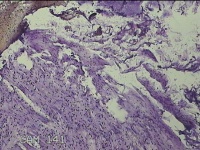

直肠息肉

性别

女

年龄

39岁

临床诊断

混合痔

一般病史

反复肛门肿物3月。

标本名称

大体所见

灰白暗红色条索状肿物5.3x2x0.8cm一个,表面糜烂,切面灰白暗红色,质软。

考虑内痔,伴出血、炎症。